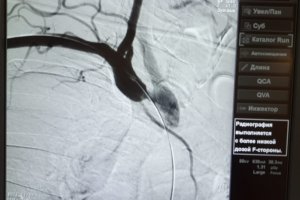

Уже несколько месяцев в центре сосудистой хирургии им. Т.Топпера работает новая супер-современная гибридная операционная! Это существенно расширило возможности центра. Уже десятки пациентов с сложнейшими патологиями сосудов получили хирургическую помощь. Хирурги центра под руководством Алексея Владимировича Светликова постоянно обучаются новым технологиям и проходят стажировки в различных клиниках по всему миру. Именно поэтому в центр сосудистой хирургии им. Т.Топпера Вы можете получить помощь, соответствующую самым современным мировым стандартам!